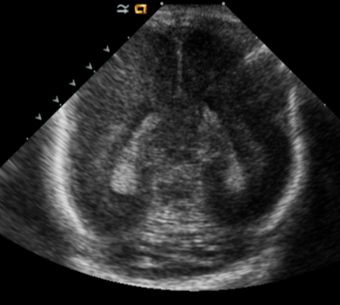

Info Images Findings Impression Reco/Acuity Case Images View Images / Launch Visage Case Notes History Full term infant. We are asked to evaluate posterior fossa cyst. Exam Gray scale and Doppler Ultrasonographic examination of the head. Prior Study N/A Dicom View Reference Material

Section 1 Submit Findings Case149 Findings Brain The brain is immature. Yes No There is under-sulcation and open sylvian fissures. Yes No There is/are multiple hypoechoic areas in the periventricular white matter. Yes No There is/are multiple hyperechoic areas in the periventricular white matter. Yes No There is diffuse cerebral edema with diffusely increased echogenicity of the brain parenchyma and loss of grey white matter differentiation. Yes No The thalami/basal ganglia are hypoechoic. Yes No There is periventricular calcification. Yes No There is intra-parenchymal calcification. Yes No CSF spaces/ventricular system There is a prominence of the extra axial fluid spaces. Yes No There are debris/septations in the extra axial fluid spaces. Yes No There are debris/septations in the ventricles. Yes No There is a subdural collection on the right/left side. Yes No There is prominence of the ventricular system. Yes No There is an asymmetry of the ventricular system. Yes No There is a cavum septum pellucidum. Yes No There is a midline shift towards right/left. Yes No The choroid plexus is bulky/lobulated. Yes No There is a choroid plexus cyst measuring… Yes No There are debris/clots in the occipital horn. Yes No There is a posterior fossa cyst measuring… Yes No The tentorium is elevated/depressed. Yes No The lateral ventricle/s are dilated. Yes No The third ventricle is dilated. Yes No The 4th ventricle is dilated. Yes No There are pseudo cysts. Yes No Germinal matrix hemorrhage (Only in the premature infants): Please do not answer if the patient is a full term. There is a germinal matrix hemorrhage, consistent with a grade I hemorrhage. Yes No There is an intraventricular extension consistent with a grade II hemorrhage. Yes No There is an intraventricular extension with the dilatation of ventricles, consistent with a grade III hemorrhage. Yes No There is an intra-parenchymal extension, consistent with grade IV hemorrhage. Yes No On color Doppler examination, the Resistive index in the anterior cerebral artery is… There is a loss of the diastolic flow on the Doppler exam. Yes No There is altered vascularity on Doppler imaging. Yes No There is an AVM in the region of… Yes No